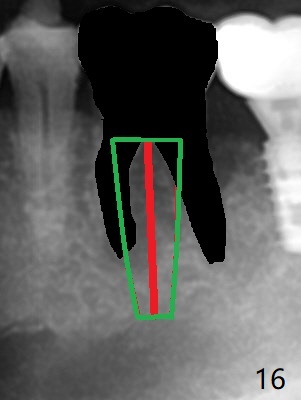

Venopuncture is conducted (Fig.1) for PRF and sticky bone (cortical chip and .5 cc ß-TCP). After use of proximators at #19, cowhorn forceps are applied, resulting in metal crown dislodgement. Since there is distal bone loss, distal socket sheath is contemplated. The tooth is sectioned. When an elevator is inserted between the roots, the distal root is loosened first. The 2 roots are removed, revealing a rounded end septum (Fig.2 S) and a larger distal socket. To avoid osteotomy deviation over the septum, a 12 mm bone trimmer is used, followed by point drill (Fig.3 *). But the lower half of the implant is deviated mesial (Fig.4) with decreased torque (~ 10 Ncm). To overcome this misfortune, the roots should not be removed until osteotomy is finished. Dual zones of bone graft is conducted. Sticky bone is placed until the plateau of the implant with a healing screw in place (Fig.4 * (bone zone)). After placement of a pair abutment, the same bone graft is packed until the margin of the abutment (Fig.5 * (soft tissue zone)). An immediate provisional is fabricated to close the socket with a piece of PRF as well. Fig.6-11 explains why the lower half of the implant deviates to the mesial socket, while Fig.12-16 illustrates how to prevent the deviation. After extraction of #19 (Fig.6,7), the crest of the septum is flattened (Fig.8 arrowhead) to prevent the initial deviation (Fig.9 red line). When a drill reaches a space (a socket, mesial in this case), the drill is deflected to the least resistant area (Fig.10 a bent red line), leading to the implant deviation apically (Fig.11 green). To prevent the apical deviation, therefore, the roots of the affected tooth is temporarily not removed (Fig.12). The osteotomy should not deviates with surgical guide because of similar density between the tooth and the bone (Fig.13). When the osteotomy is finished (Fig.14), the roots are extracted (Fig.15). The implant to be placed should not have deviation (Fig.16 green). The papillae are maintained by the immediate provisional 11 days postop (Fig.17). The incompletely seated abutment at #18 (Fig.5 <) is reseated completely 6 months postop (Fig.18). Crestal bone forms distal to #19 implant. There is no bone loss 4 months and 3 years 1 month post cementation at #19 and 18, respectively (Fig.19,20).